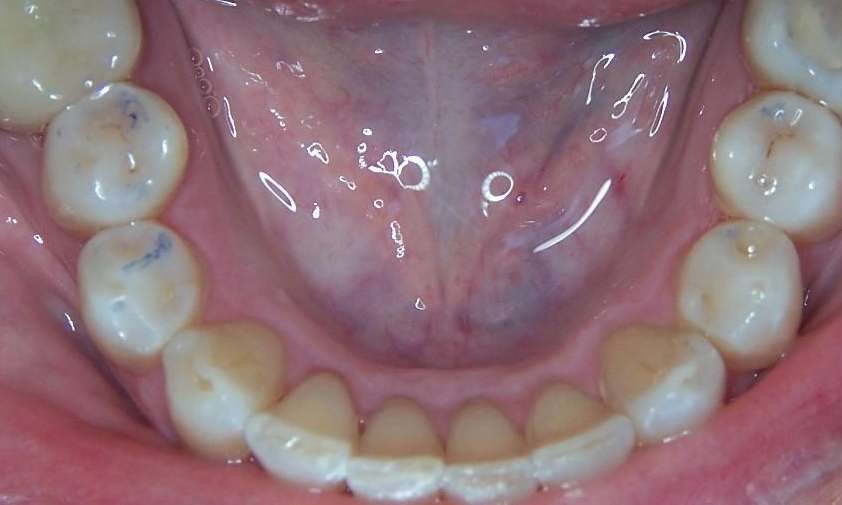

A long time patient of ours had noticed her teeth shifting and her bite changing. She noticed that her front teeth were colliding more than they used to which could be causing some chipping of her bottom teeth. As well, her bottom teeth were crowded and hard to floss. We suggested clear aligners in Los Gatos as a service to improve the function and health of her gums.

As a very compliant patient, the clear aligner process took about 10 months. After completion, our patient felt that her teeth were straighter, and had a more balanced and softer bite. She also started flossing more regularly because it was much easier to do now, which has led to improved gum health.